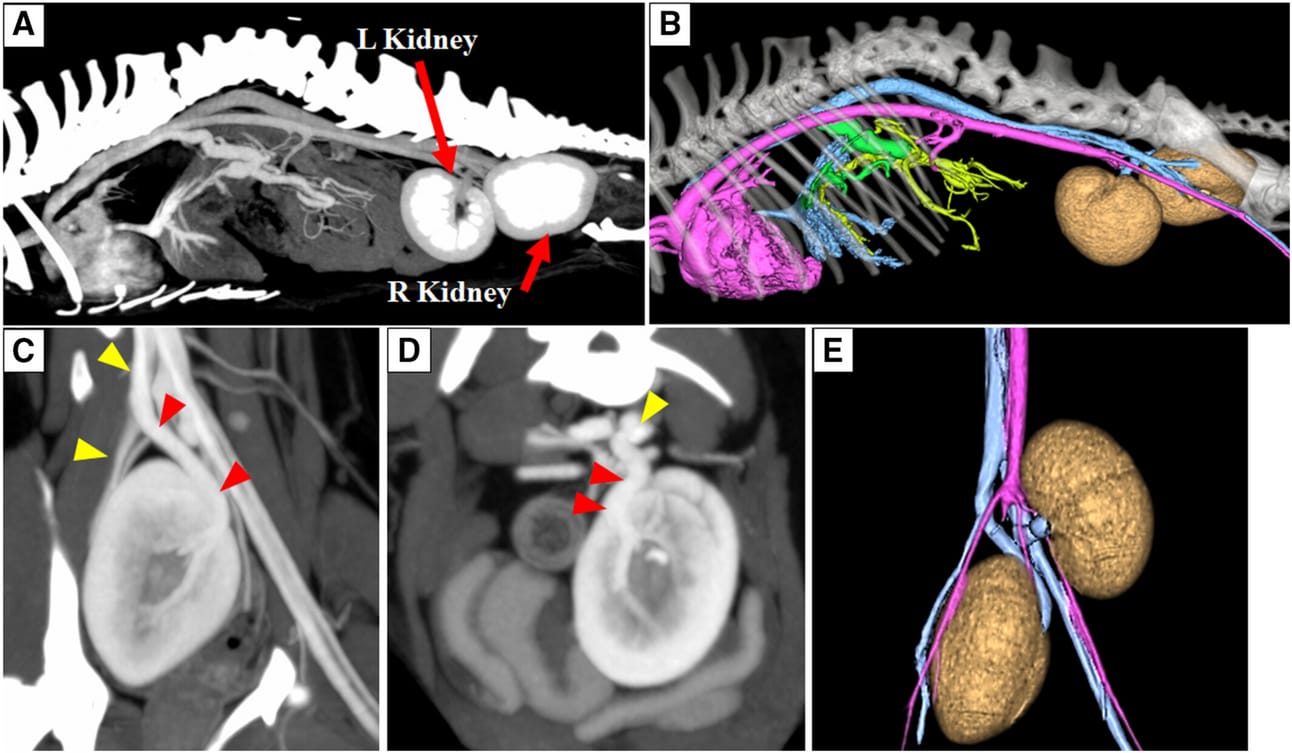

CT imaging of this case. The post contrast sagittal maximum intensity projection (MIP) image (soft tissue window) (A): the left kidney was located on the level of L6-7, and the right kidney was located on the level of S1. All veins caudal to the hepatic vein that would normally anastomose with the CVC were anastomosed with azygos vein. The volume rendered reconstruction image of left side view (B): green region; shunt vessel, blue region; systemic vein, yellow region; portal vein, pink region; aorta and heart. The post contrast dorsal MIP image of right kidney (soft tissue window) (C): the right renal veins anastomosed to the right common iliac vein; yellow arrowhead; the right common iliac vein, red arrowhead; the right renal veins. The post contrast transverse MIP image of left kidney (soft tissue window) (D): the left renal veins anastomosed to the left common iliac vein; yellow arrowhead; the left common iliac vein, red arrowhead; the left renal veins. The volume rendered reconstruction image of ventral side view (E): blue region; vein, pink region; aorta. Sagittal multi-planer reconstruction image of thoracolumbar spine (bone window)

- Ectopic positioning of both kidneys; the left kidney was located on the left side of the bladder at the level of L6-L7, and the right kidney was found caudal to the bladder in the pelvic cavity. Both kidneys were correctly connected to the bladder via their ureters, and their arteries and veins anastomosed to the external iliac arteries and common iliac vein, respectively.